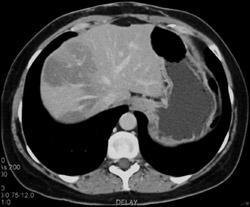

Prior Hepatic Infarct in Transplanted Liver